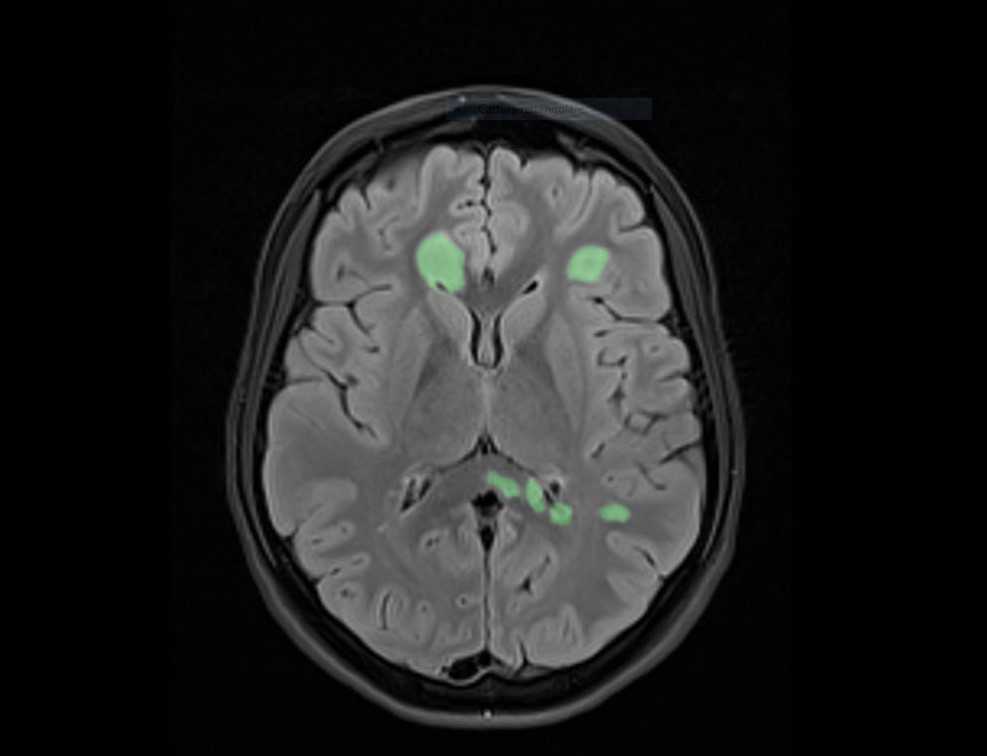

La sclerosi multipla (SM) è una malattia infiammatoria del sistema nervoso centrale caratterizzata dalla perdita di mielina (la sostanza bianca che riveste come una guaina le fibre nervose) in più aree del cervello e del midollo spinale, con la formazione di lesioni (placche) che possono evolvere da infiammatorie a croniche. La SM può manifestarsi con sintomi diversi a seconda delle regioni interessate, come difficoltà a camminare, problemi di equilibrio o deficit della vista. Sebbene possa insorgere a qualsiasi età, colpisce principalmente giovani adulti tra i 20 e i 40 anni. Nel 10% dei casi, la malattia si manifesta tra i 10 e i 18 anni, mentre è più raro l’esordio prima dei 10 anni.